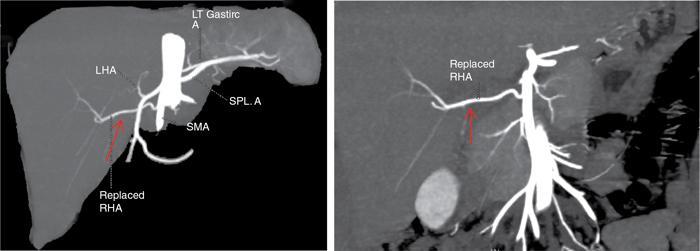

Ritu K. Kashikar, Shrinivas B. Desai Imaging is the mainstay of noninvasive diagnosis of the spectrum of abdominal pathologies or proving absence off thereof. Knowledge of normal anatomy and important normal variants is thus essential for the radiologist in order to avoid misinterpretation or erroneous diagnosis. This chapter highlights the normal anatomy of the hepatobiliary systems including the blood vessel and draining ducts and discusses relevant anatomical variants which may have important clinic implications. The liver is the largest abdominal organ, occupying the right upper abdominal quadrant and is in close approximation with the diaphragm, stomach and the gallbladder. It is largely covered by the costal cartilages. The liver is encapsulated by Glisson’s capsule which is a dense layer of connective tissue. It is covered by peritoneum, except in the regions of gallbladder fossa, fossa for inferior vena cava (IVC), and the bare area. The bare area is the posterocranial aspect of the liver, adjacent to the dorsal body wall, which is not covered by peritoneum. The liver has two surfaces, the convex diaphragmatic surface and a concave visceral surface. The slit in the hepatic hilum is called the porta hepatis and is penetrated by the right and left hepatic ducts (LHDs), hepatic artery and portal vein (PV). The distal portion of the lesser omentum is called the hepatoduodenal ligament and contains the common bile duct (CBD), hepatic artery, PV, nerves of liver and lymphatics. The liver has dual blood supply with hepatic artery providing 25% of hepatic blood and rest by portal vein (Fig. 9.2.1). Five ligaments connect the liver to the undersurface of the diaphragm. These include the falciform, the coronary and two lateral ligaments, all of which are peritoneal folds. The fifth ligament is a fibrous cord-like structure and represents the obliterated umbilical vein. The peritoneum invaginates into the liver parenchyma leading to formation of fissures. There are four normal fissures: fissures for the ligamentum teres, ligamentum venosum and gallbladder and the transverse fissure (Fig. 9.2.2). The liver is organized into microscopic functional units called lobules or acini. A central terminal hepatic venule surrounded by four to six terminal portal triads form a polygonal unit called the hepatic lobule. The terminal portal triad branches line the periphery of the unit. Between the terminal portal triads and the central hepatic venule the hepatocytes are arranged in one cell thick plates, surrounded by sinusoids. The blood flows from the terminal portal triad through sinusoids into terminal hepatic venule. Bile formed within the hepatocytes empties into terminal canaliculi which coalesce into the bile ducts (Fig. 9.2.3). This structure of the functional hepatic unit forms the basis of various functions of the liver. The normal relations of the liver are: The liver can be divided into right, left and caudate lobes. The right and left lobes are separated by the interlobular fissure and is oriented along a line passing through the gallbladder fossa inferiorly and the middle hepatic vein (MHV) superiorly (Fig. 9.2.4). This plane runs from the left of the IVC to the left of the gallbladder fossa and is a called the Cantlie’s line. Use of standardized, segmental anatomy is imperative because it facilitates communication and treatment planning. The segmental anatomy of liver is primarily based on vascular anatomy. The right lobe is divided into anterior and posterior sectors by of the right hepatic vein (RHV). The left lobe is divided into medial and lateraI sectors by an oblique plane connecting the left hepatic vein (LHV) and the falciform ligament. The liver is divided into upper and lower segments at the level of main portal vein (MPV) bifurcation (Fig. 9.2.5). Various systems are used in classification of liver anatomy. These are discussed in Table 9.2.1. The Couinaud’s system is the most commonly used and divides eight sections/segments which are discussed in details below (Table 9.2.2). 1. Segment 1 – Caudate lobe Bounded anteriorly and medially by the fissure for ligamentum venosum (Fig. 9.2.6). 2. Segment 2: Superior segment of the left lateral sector/section Bounded medially by falciform ligament and inferiorly by plane of MPV, also known as the posterior lateral sector (Bismuth, FCAT) (Fig. 9.2.7). 3. Segment 3: Inferior segment of left lateral sector/section Bounded medially by the falciform ligament and superiorly by the plane of the MPV bifurcation, also referred to as lateral anterior sector (Bismuth, FCAT) (Fig. 9.2.8). 4. Segment 4: Left medial sector/section Bounded laterally by falciform ligament and medially by Cantlie’s line (Fig. 9.2.9). 5. Segment 5: Inferior segment of the right anterior sector/section Bounded anteriorly by the gallbladder fossa and posteriorly by the plane of the RHV, superiorly bounded by the plane of MPV bifurcation (Fig. 9.2.10). 6. Segment 6: Inferior segment of the right posterior sector/section Bounded anteriorly by plane of the RHP and superiorly by the plane of the MPV bifurcation (Fig. 9.2.11). 7. Segment 7: Superior segment of the right posterior sector/section Bounded anteriorly by the plane of the RHV and inferiorly by the plane of the MPV bifurcation (Fig. 9.2.12). 8. Segment 8: Superior segment of the right anterior sector/section Bounded anteriorly by the plane of the gallbladder fossa and MHV, posteriorly bounded by the plane of the RHV and inferiorly by the plane of the MPV bifurcation (Fig. 9.2.13). Owing to its broad area of contact with the anterior abdominal wall, the liver is an ideal organ for evaluation with sonography. Ultrasound is commonly used for evaluation of size of the liver. On longitudinal scans obtained through the midhepatic line, if the liver measures 13 cm or less, it is normal in 93% of individuals (Fig. 9.2.14). The size of liver in various planes is discussed in chapter on normograms. When the area of contact between the liver and the anterior border of the right kidney, exceeds below two thirds of the kidney, the liver is considered as enlarged. The normal liver is homogeneous with fine echoes and appears evenly bright. The hepatic veins, PV and fissures interrupt the homogeneity of the liver parenchyma (Fig. 9.2.15). The parenchymal echogenicity may vary depending on the equipment, transducer and gain settings and should be judged by comparison with internal references like right renal cortex, body of the pancreas and PV walls. When compared with the adjacent normal right renal cortex the liver normally appears hyperechoic or isoechoic. The pancreas in a young individual is hypoechoic compared to the liver, and isoechoic in middle aged adults. As age progresses and fatty infiltration of the pancreas occurs, the pancreas appears hyperechoic to the liver. The liver is hypoechoic to the spleen. The normal liver reveals a density of 55–65 HU on nonenhanced scan and should appear homogenous with the exception of hypodensity in the regions of vessels and fissures. The liver parenchymal enhancement is minimal the arterial phase, with increase in density by only approximately 10 HU. This phase is usually to access vascular anatomy and to detect neovascular enhancing lesion like HCC, metastasis. Considering the fact that 75% of heptic venous supply is from the PV, the normal hepatic parenchyma shows maximum enhancement in the portal venous phase. During the venous/delayed phase the hepatic attenuation starts falling (Fig. 9.2.16). The hepatic fissures appear as linear fat containing structures. All the four fissures are well identifies on CT (Figs. 9.2.17–9.2.20). Normal liver should demonstrate uniform T1 signal similar or isointense to the paraspinal muscles and slightly hyper intense to the spleen. No signal drop should be seen on in or opposite phase. On T2W1 images liver appears slightly hyperintense to paraspinal muscles, isointense to pancreas and hypointense to spleen (Fig. 9.2.21). Following administration of extracellular contrast agents the normal liver parenchyma enhances on PV phase similar to that seen on CT. The arterial phase is preserved to determining vascular anatomy, variants and tumoural enhancement. Gadoxetic acid (Eovist) and gadobenate dimeglumine (MultiHance) are hepatobiliary agents showing excretion by the liver. In the case of gadoxetic acid, hepatic excretion is ~50%, which allows imaging in the hepatobiliary phase at ~20 minutes following injection. Gadobenate has only 3%–5% biliary excretion with hepatobiliary phase at approximately 40 minutes (Fig. 9.2.22). This property makes these agents useful in detection of nonhepatocyte containing lesions which appear hypointense to background liver on hepatobiliary phase. Hepatic anatomic variants are relatively common and represent normal interindividual variation of liver morphology. Normal Anatomic Variants Anatomic anomalies Accessory and pseudofissures may be seen in the liver. True accessory fissures result from infolding of the peritoneum usually along the undersurface of the liver and are rare. The inferior accessory fissure is the commonest accessory fissure and divides the posterior segment of the right hepatic lobe into lateral and medial portions. Diaphragmatic slips may cause indentation over the liver surface and are not commonly seen on imaging (Fig. 9.2.23). Leftward extension of the lateral segment of the left hepatic lobe appearing as a crescentic density that wraps around the spleen is referred to as sliver of liver. The left lobe of the liver may exhibit various forms: leaf like; spatular; truncated pyramid/wedge shaped; and a bifid appearance (Fig. 9.2.24). Elongated left lobe may be mimic splenomegaly, perisplenic hypoechoic collections or less commonly tumours. Imaging clues to diagnosis are establishing contiguity with liver and visualization of parenchymal vessels coursing through. The portion of the liver that extends medially from the right lobe between the IVC and fissure for ligamentum venosum is called the caudate lobe. The caudate lobe is divided inferiorly into a lateral caudate process and a medial papillary process. The medial papillary process projects medially towards the pancreatic head and has applied importance (Fig. 9.2.25). Riedel’s lobe is a tongue-like projection from the anterior aspect of the right lobe and the most common accessory lobe of the liver. It is seen most frequently in asthenic women. The reported prevalence of RL, ranges from 3.3% to 14.5% and the prevalence is higher in women than in men. It can be 20 cm or more in length and may extend up to the iliac fossa. It is usually asymptomatic and is discovered incidentally (Fig. 9.2.26). Accessory liver lobes are defined as a supernumerary lobe of normal hepatic parenchyma in continuity with the liver. This is a rare entity and usually occurs as a result of congenital ectopic hepatic tissue, although rarely may occur as a result of trauma or surgery. Various systems are proposed for classification of ALL. Another method of classification has been proposed based on biliary drainage and presence or absence of capsule. Accessory lobes can be readily diagnosed and characterized on CT or magnetic resonance imaging (MRI) done for related or unrelated conditions. CT shows the lesion as a soft–tissue density mass attached to the liver and isodense to the organ. The portal/hepatic venous branches can be seen coursing through it, in contiguity with the liver (Fig. 9.2.27). The coeliac axis trifurcates into common hepatic, splenic and left gastric arteries at the level of T12–L1. The common hepatic artery becomes the proper hepatic artery after origin of the gastro-duodenal artery. The hepatic artery proper ascends anterior to the PV and medial to the CBD and divides in to right and left hepatic artery (LHA). Occasionally the middle hepatic (segment 4) artery arises from hepatic artery proper. The hepatic artery appears as a tubular hypoechoic structure and shows antegrade flow on Doppler (Fig. 9.2.28). Normally the resistive index is low ranging between 0.55 and 0.7. The hepatic artery, its anatomy, branches, course, calibre are best evaluated on arterial phase of dynamic CT (Fig. 9.2.29). This is also the preferred modality prior to hepatobiliary surgical planning. Contrast-enhanced MRI also shows the above details but spatial resolution is lower. Road map of the arterial vascularity of the donor and recipient is a prerequisite for transplant surgery and complex hepatobiliary surgery. Detailed hepatic arterial anatomy and its variations have its significance in liver surgeries and interventional hepatic procedures, relative to the hepatic lobe involved. A classification method was described by Michel et al. in 1955, and is discussed in Table 9.2.3 (Fig. 9.2.30). I: standard anatomy ~60% (range 55%–61%) II: replaced LHA ∼7.5% (range 3%–10%) III: replaced RHA ~10% (range 8%–11 %) IV: replaced RHA and LHA ~1% V: accessory LHA from LGA ~10% (range 8%–11%) VI: accessory RHA from SMA ~5% (range 1.5%–7%) VII: accessory RHA and LHA ~1% VIII: accessory RHA and LHA and replaced LHA or RHA ~2.5% IX: CHA replaced to SMA ~3% (range 2%–4.5%) X: CHA replaced to LGA ~0.5% Other unclassified variants are: The two most common variants are the replaced right hepatic artery (RHA) arising from the SMA (Fig. 9.2.31) and replaced LHA arising from the left gastric artery (Figs. 9.2.32–9.2.34). Segment 4 artery – Middle hepatic artery (MHA) The middle hepatic artery usually arises from the LHA, it may, however, arise from the RHA (Fig. 9.2.35). The knowledge regarding origin of MHA is imperative in transplant surgery. The MHA can arise from RHA in Patients with replaced LHA. In patients with replaced RHA, the MHA arises from LHA (Fig. 9.2.36). Because of the considerable variability of hepatic arterial anatomy, assessment of this anatomy is crucial in the preoperative evaluation of potential living liver donors. Relevance of donor and recipient arterial anatomy is discussed in details in chapter on liver transplant. The relationship between the arterial variant and tumour is important to establish prior to major surgeries. Injuries to aberrant hepatic vessels and secondary ischaemic biliary strictures can be avoided. A replaced RHA has a more posterior course and long length. This variant may be advantageous in patients undergoing right lobar resection. However, there is greater propensity of involvement of replaced RHA by pancreatic head. The radiologist must be vigilant in reporting this variant (Fig. 9.2.37). Accessory RHA can, however, be sacrificed even if encased by neoplasm. An accessory LHA needs to be ligated separately in surgeries where blood supply in the porta hepatis is occluded. Replaced LHA from LGA maybe injured in case of surgeries at the level of hiatus. Hence this variant should be informed to surgeon in patients undergoing gastric surgeries. Preoperative mapping of the hepatic arterial anatomy prior to placement of intraarterial chemotherapy pumps is essential because it helps in deciding whether the candidate is suitable for the procedure and also if technical modifications are needed. The intraarterial infusion pump should be placed in the dominant hepatic artery as proximal as possible, but beyond GDA origin. Inpatients with standard anatomy, the pump is usually placed in the hepatic artery prior just after GDA origin. The location of pump can be modified in patients with variant anatomy, based on origin of GDA and dominant hepatic vessel. The PV is the main vessel in the portal venous system and drains blood from the gastrointestinal tract and spleen to the liver.